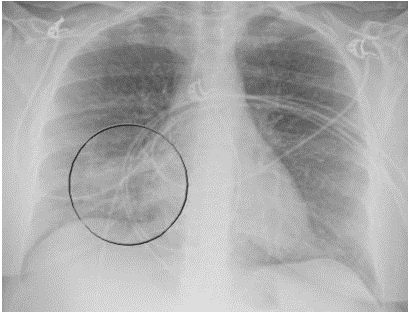

A 52-year-old Caucasian female, who is a resident of southwestern Ohio, presented to the emergency room with a chief complaint of a two-week history of right-sided chest pain, which had progressively worsened despite two courses of antibiotics and pain medications following her two recent visits to the emergency department. She also described subjective fever, shortness of breath, nonproductive cough and weight loss of 4 kg over the last two weeks. She was a smoker of ½ pack per day for 20 years and quit smoking 4 weeks ago. The patient’s past medical history includes anxiety, depression, gastroesophageal reflux disease, hypertension, mitral valve prolapse, and migraine headache. Her chest pain started in early September, and it was described as stabbing and pleuritic, which was also noted to be reproducible to palpation of the chest wall. She was seen first at the emergency department two weeks prior to the current presentation for evaluation of the right-sided chest pain. Still, at that time, there was no fever or cough, and her vitals were stable with Oxygen Saturation 94% on room air, although her laboratory testing was significant for leukocytosis with (WBC):16.6 K/UL with 68.5% neutrophils. Chest-X-ray demonstrated an infiltrate in the right lung base medially, while CT–chest angiography demonstrated no evidence of pulmonary embolism and right middle lobe consolidation consistent with pneumonia. There was no mediastinal or hilar lymphadenopathy, (Figures 1 and 2).

Figure 1. Portable Chest X-ray showing infiltrate in right lung base medially.